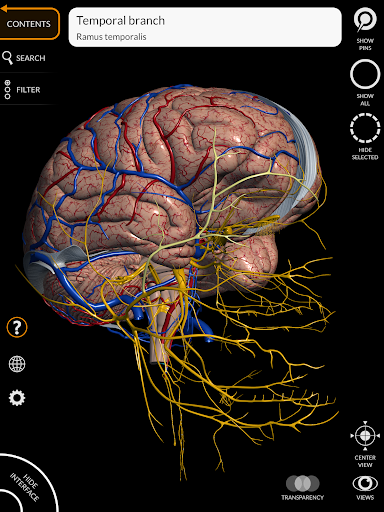

"Anatomy 3D Atlas" memungkinkan Anda mempelajari anatomi manusia dengan cara yang mudah dan interaktif.

Melalui antarmuka yang sederhana dan intuitif, Anda dapat mengamati setiap struktur anatomi dari sudut mana pun.

Model 3D anatomi sangat terperinci dan memiliki tekstur hingga resolusi 4k.

Pembagian berdasarkan wilayah dan tampilan yang telah ditetapkan sebelumnya memudahkan pengamatan dan studi bagian tunggal atau kelompok sistem dan hubungan antara organ yang berbeda.

MODEL ANATOMI 3D

saraf • Sistem pernapasan • Sistem pencernaan • Sistem urogenital (pria dan wanita) • Sistem endokrin • Sistem limfatik • Sistem mata dan telinga FITUR • Antarmuka yang sederhana dan intuitif • Putar dan perbesar setiap model dalam ruang 3D • Opsi untuk menyembunyikan atau mengisolasi satu atau beberapa model yang dipilih • Filter untuk menyembunyikan atau menampilkan setiap sistem • Fungsi pencarian untuk menemukan setiap bagian anatomi dengan mudah • Fungsi penanda untuk menyimpan tampilan khusus • Rotasi cerdas yang menggerakkan pusat rotasi secara otomatis • Fungsi transparansi • Visualisasi otot melalui tingkat lapisan dari yang superfisial hingga yang terdalam • Dengan memilih model atau pin, istilah anatomi terkait akan muncul • Deskripsi otot: asal, • Tampilkan/ Sembunyikan antarmuka UI (sangat berguna dengan layar kecil) MULTIBAHASA • Istilah anatomi dan antarmuka pengguna tersedia dalam 11 bahasa: Latin, Inggris, Prancis, Jerman, Italia, Portugis, Turki, Rusia, Spanyol, Mandarin, Jepang, dan Korea • Istilah anatomi dapat ditampilkan dalam dua bahasa secara bersamaan PERSYARATAN SISTEM • Android 8.0 atau yang lebih baru, perangkat dengan RAM minimal 3GB Reversi